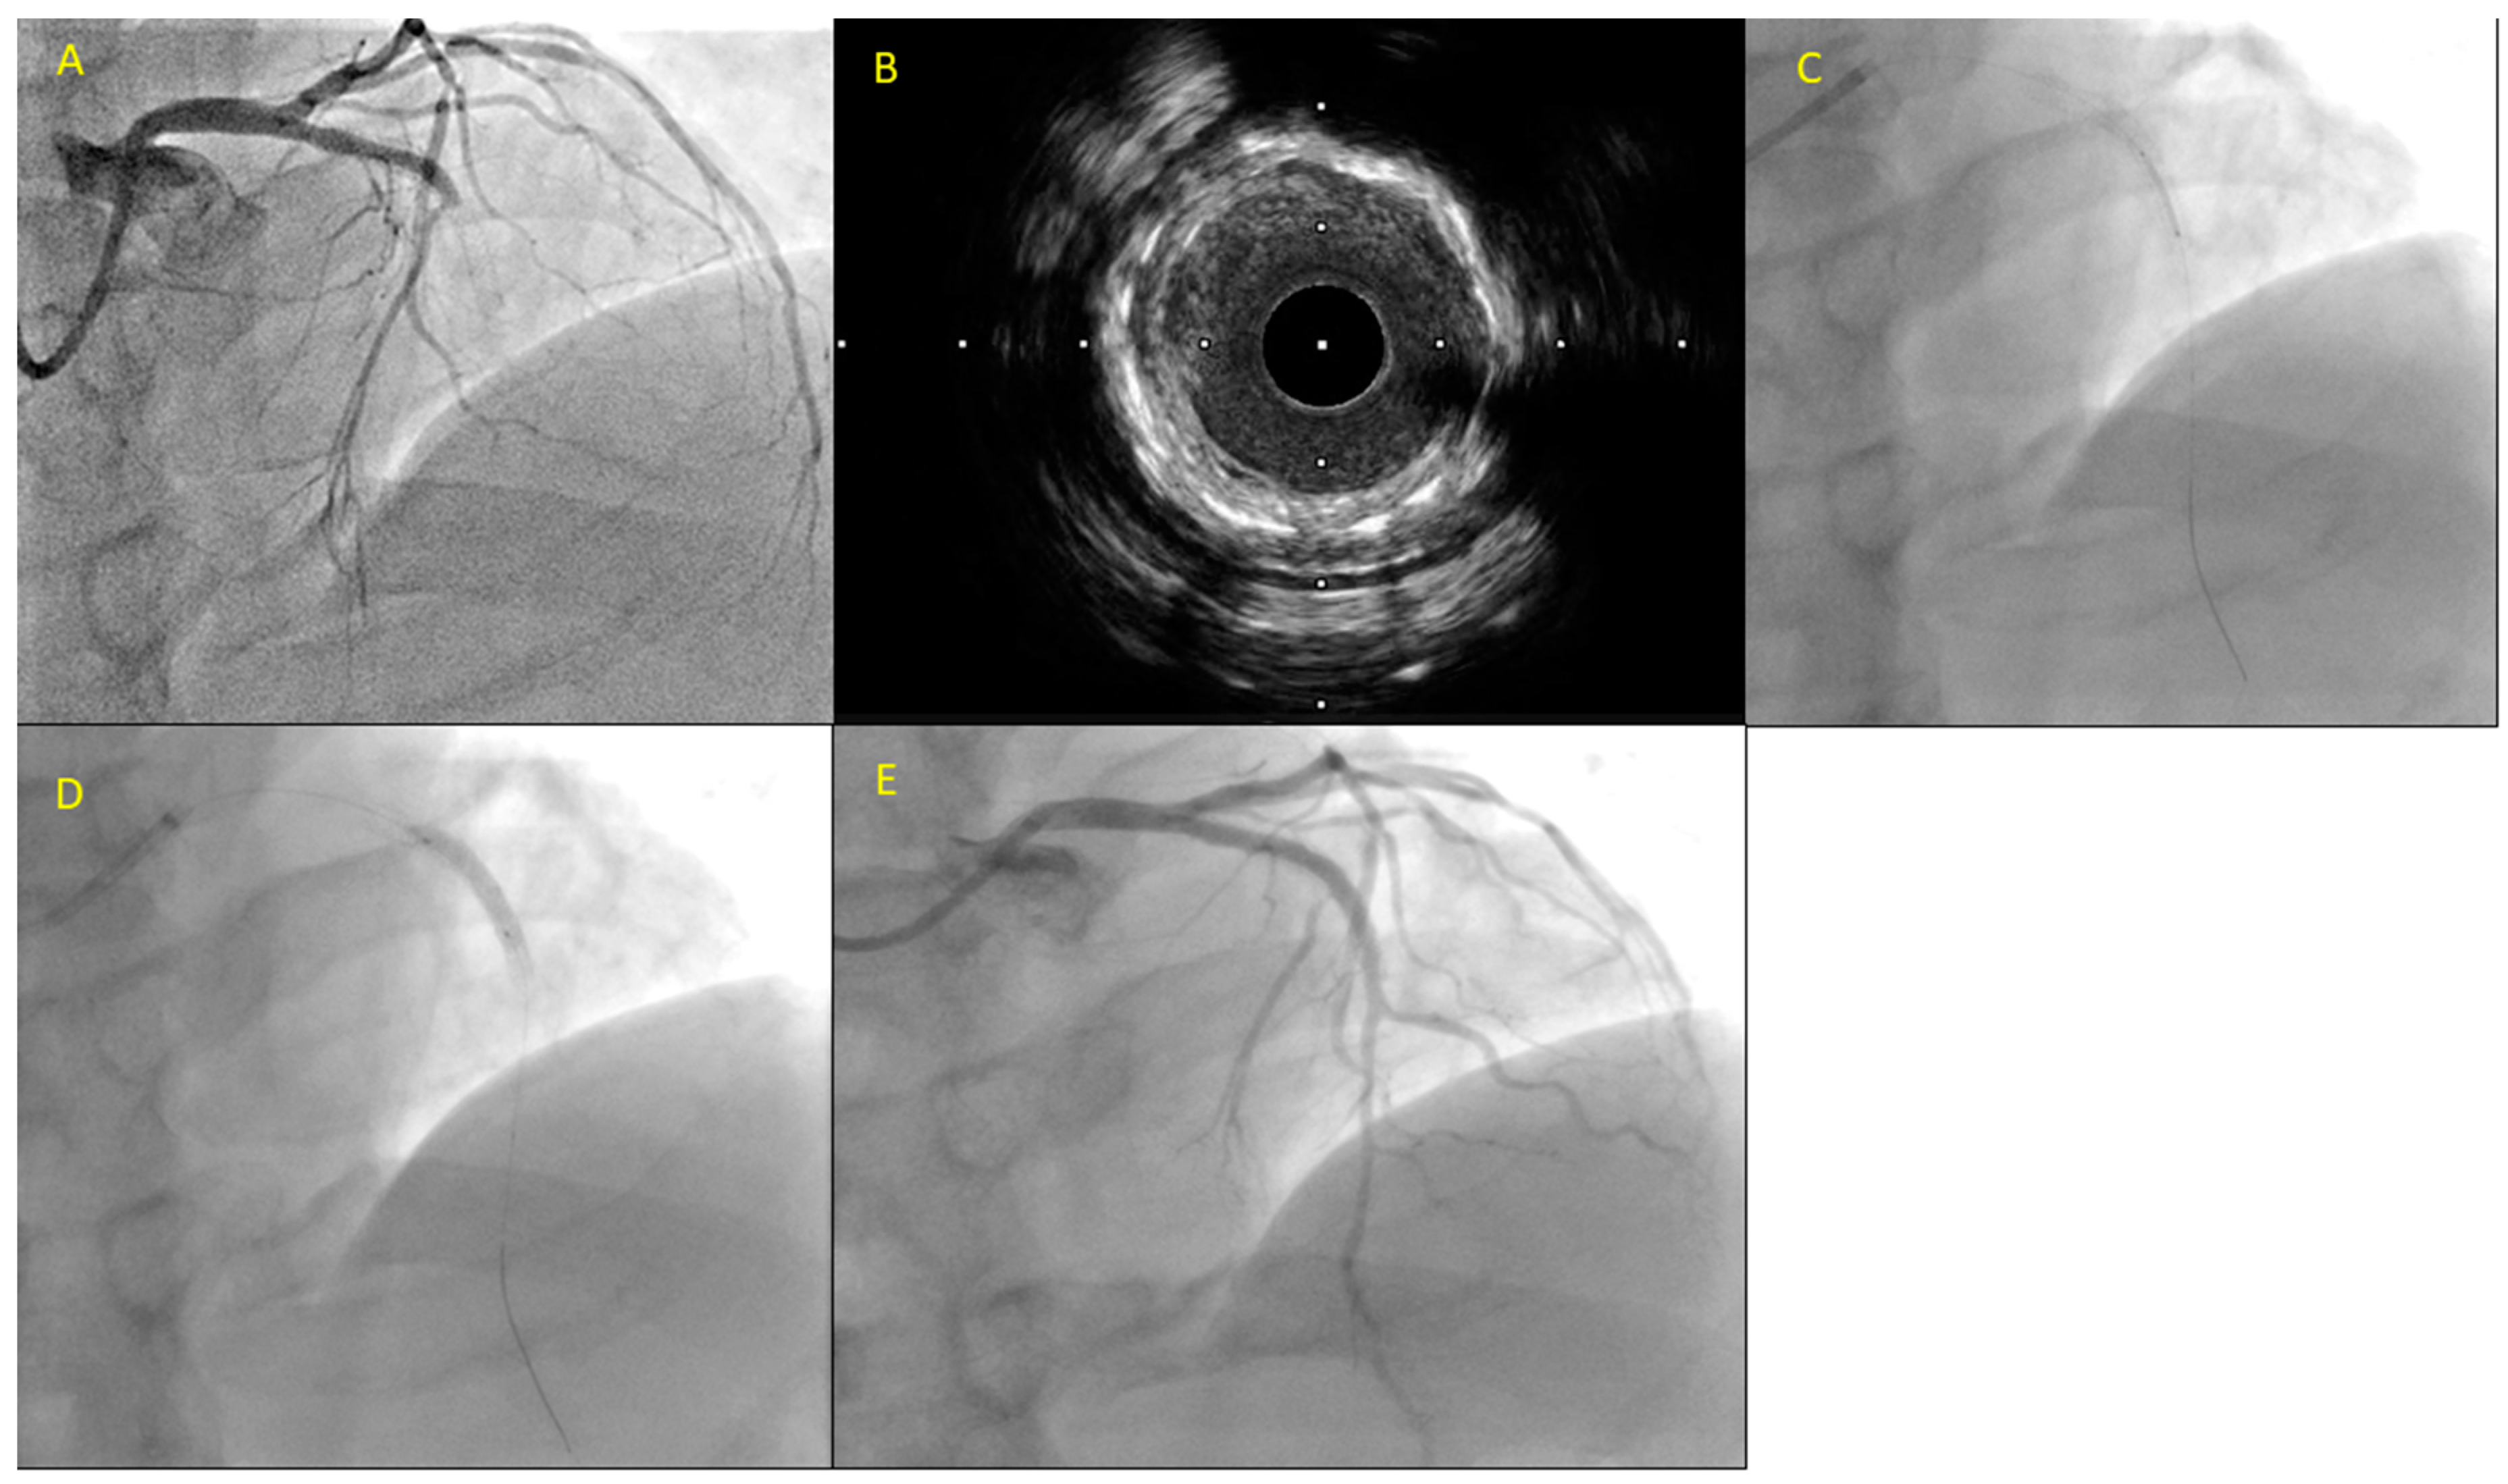

- Jia, H.; Dai, J.; He, L.; Xu, Y.; Shi, Y.; Zhao, L.; Sun, Z.; Liu, Y.; Weng, Z.; Feng, X.; et al. EROSION III: A Multicenter RCT of OCT-Guided Reperfusion in STEMI With Early Infarct Artery Patency. JACC Cardiovasc. Interv. 2022, 15, 846–856. [Google Scholar] [CrossRef] [PubMed]

- Jia, H.; Dai, J.; Hou, J.; Xing, L.; Ma, L.; Liu, H.; Xu, M.; Yao, Y.; Hu, S.; Yamamoto, E.; et al. Effective anti-thrombotic therapy without stenting: Intravascular optical coherence tomography-based management in plaque erosion (the EROSION study). Eur. Heart J. 2017, 38, 792–800. [Google Scholar] [CrossRef] [PubMed]

- Xing, L.; Yamamoto, E.; Sugiyama, T.; Jia, H.; Ma, L.; Hu, S.; Wang, C.; Zhu, Y.; Li, L.; Xu, M.; et al. EROSION Study (Effective Anti-Thrombotic Therapy Without Stenting: Intravascular Optical Coherence Tomography-Based Management in Plaque Erosion): A 1-Year Follow-Up Report. Circ. Cardiovasc. Interv. 2017, 10, e005860. [Google Scholar] [CrossRef]

- He, L.; Qin, Y.; Xu, Y.; Hu, S.; Wang, Y.; Zeng, M.; Feng, X.; Liu, Q.; Syed, I.; Demuyakor, A.; et al. Predictors of non-stenting strategy for acute coronary syndrome caused by plaque erosion: Four-year outcomes of the EROSION study. EuroIntervention 2021, 17, 497–505. [Google Scholar] [CrossRef]